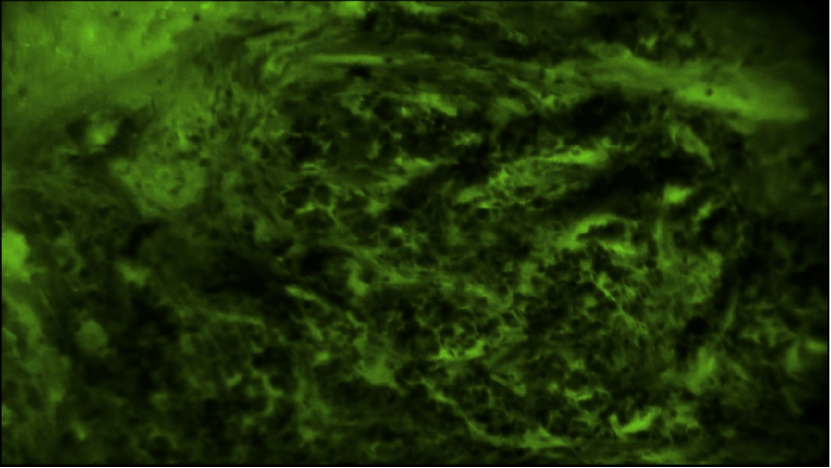

EndoSCell?鏡下常見的乳腺浸潤性癌腫瘤細胞圖像:細胞核大大小小且密度很高